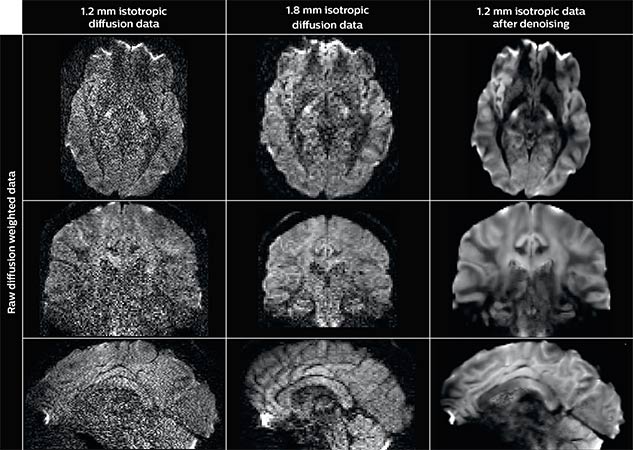

Denoising to improve quality

Using a non-local spatial and angular block matching technique to denoise raw diffusion weighted images. allows to push acquisition to lower spatial resolution and read human-connectome-project-like resolution from standard Philips Ingenia 3.0T MRI scanner.

The data were acquired with spatial resolution of 1.2 x 1.2 x 1.2 mm in 13 minutes for 40 full brain DWI with b 1000 and one with b 0